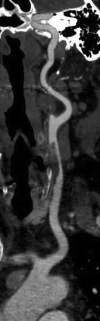

Results: During the study period, 424 patients underwent 499 arterial duplex, computed tomography angiogram, or magnetic resonance angiography imaging studies with an overall 9.4% positive rate for arterial thromboembolism. Of the 40 patients with arterial thromboembolism, 25 (62.5%) were SARS-CoV-2 negative or admitted for unrelated reasons and 15 (37.5%) were SARS-CoV-2 positive. The odds ratio for arterial thrombosis in COVID-19 was 3.37 (95% confidence interval, 1.68-6.78; P = .001). Although not statistically significant, in patients with arterial thromboembolism, patients who were SARS-CoV-2 positive compared with those testing negative or not tested tended to be male (66.7% vs 40.0%; P = .191), have a less frequent history of former or active smoking (42.9% vs 68.0%; P = .233) and have a higher white blood cell count (14.5 vs 9.9; P = .208). Although the SARS-CoV-2 positive patients trended toward a higher the neutrophil-to-lymphocyte ratio (8.9 vs 4.1; P = .134), creatinine phosphokinase level (359.0 vs 144.5; P = .667), C-reactive protein level (24.2 vs 13.8; P = .627), lactate dehydrogenase level (576.5 vs 338.0; P = .313), and ferritin level (974.0 vs 412.0; P = .47), these differences did not reach statistical significance. Patients with arterial thromboembolic complications and SARS-CoV-2 positive when compared with SARS-CoV-2 negative or admitted for unrelated reasons were younger (64 vs 70 years; P = .027), had a significantly higher body mass index (32.6 vs 25.5; P = .012), a higher d-dimer at the time of imaging (17.3 vs 1.8; P = .038), a higher average in hospital d-dimer (8.5 vs 2.0; P = .038), a greater distribution of patients with clot in the aortoiliac location (5 vs 1; P = .040), less prior use of any antiplatelet medication (21.4% vs 62.5%; P = .035), and a higher mortality rate (40.0% vs 8.0%; P = .041). Treatment of arterial thromboembolic disease in COVID-19 positive patients included open thromboembolectomy in six patients (40%), anticoagulation alone in four (26.7%), and five (33.3%) did not require or their overall illness severity precluded additional treatment.

Conclusions: Patients with SARS-CoV-2 are at risk for acute arterial thromboembolic complications despite a lack of conventional risk factors. A hyperinflammatory state may be responsible for this phenomenon with a preponderance for aortoiliac involvement. These findings provide an early characterization of arterial thromboembolic disease in SARS-CoV-2 patients.